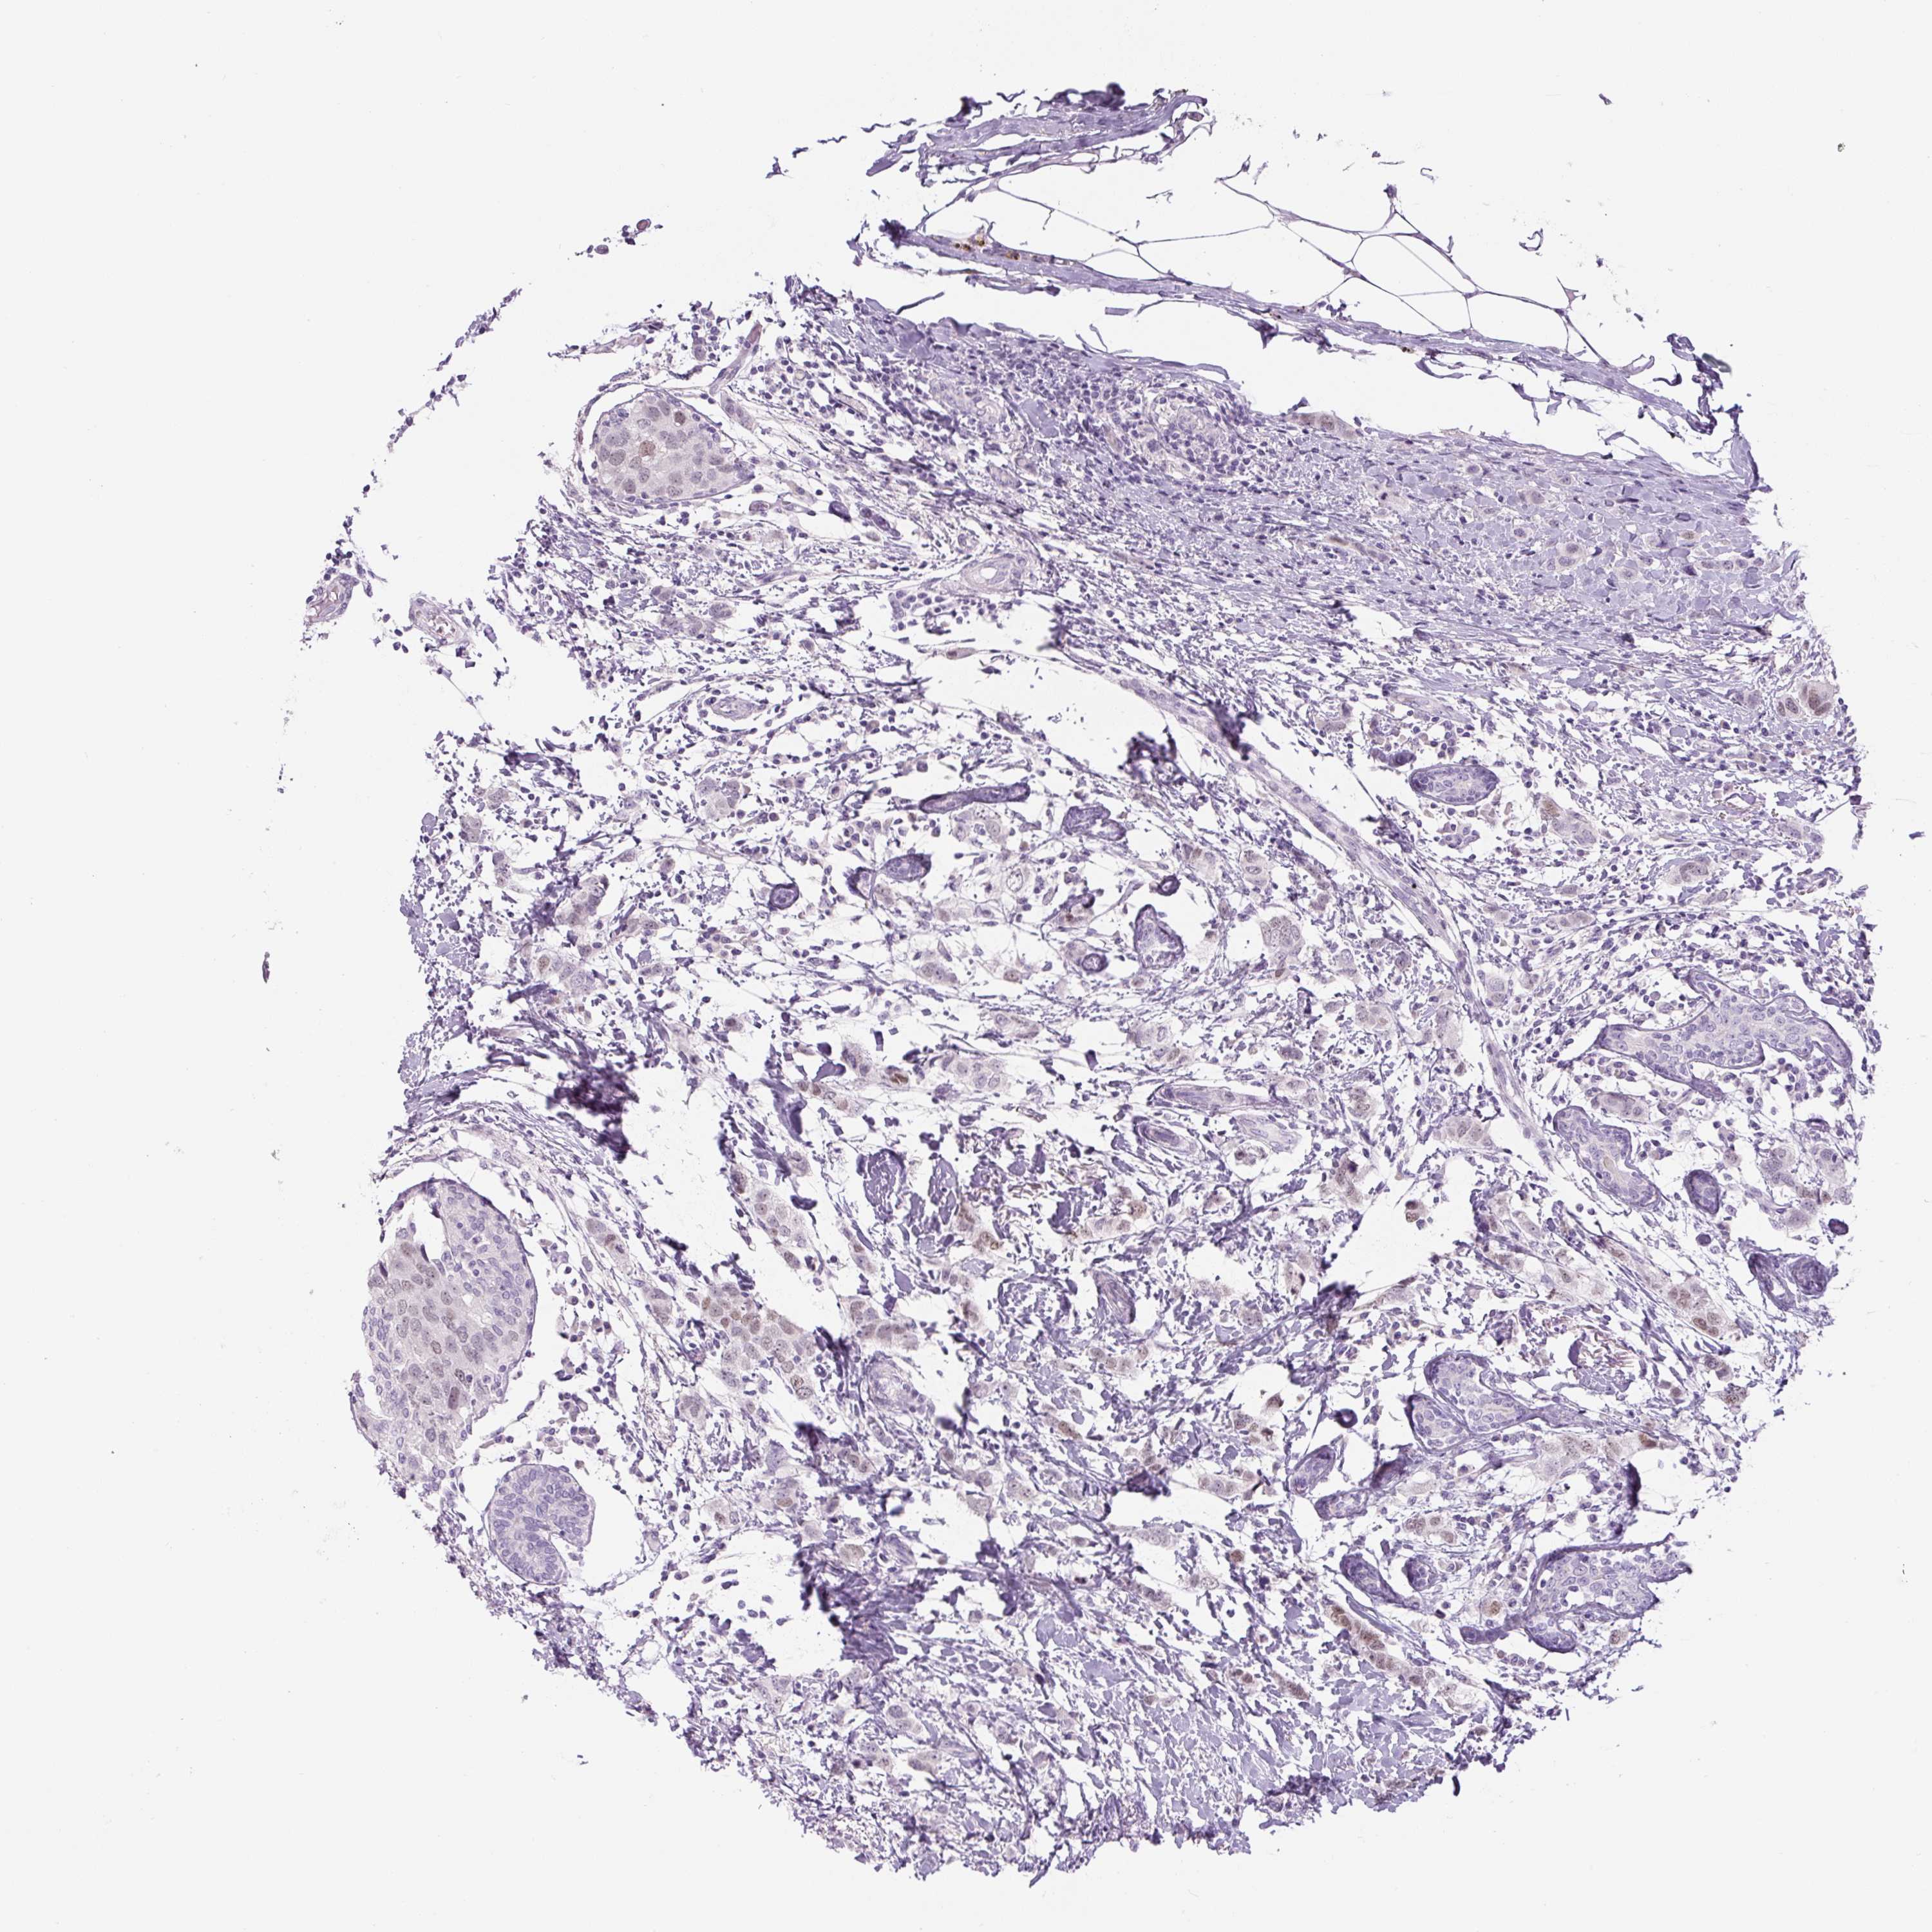

BRCA TCGA BRCA VALIDATION PROTEIN EXPRESSION

Breast cancer

Human cancer